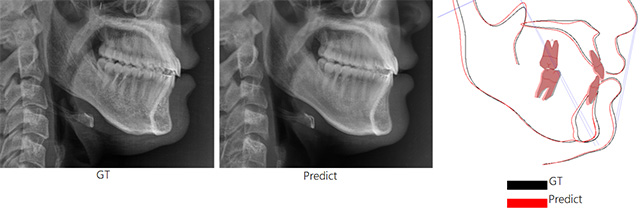

• (왼쪽부터) AI가 예측한 수술 후 영상, 실제 수술 후 영상, 두 영상 간 차이를 보여주는 이미지 /이미지 제공=서울아산병원

▲ (왼쪽부터) AI가 예측한 수술 후 영상, 실제 수술 후 영상, 두 영상 간 차이를 보여주는 이미지 /이미지 제공=서울아산병원

연구팀은 AI 모델의 정확도 검증을 위해 교정과 전문의 2명과 구강악안면외과 전문의 2명이 AI 예측 영상과 실제 영상을 구분하는 테스트를 진행했다. 그 결과 전문의가 예측 영상과 실제 영상을 구분한 정확도는 48%로, 두 영상을 거의 구별하지 못했다. 실제 예측 영상과 실제 촬영 영상의 계측점 간 평균 오차는 대부분 1.5mm 이하였다.